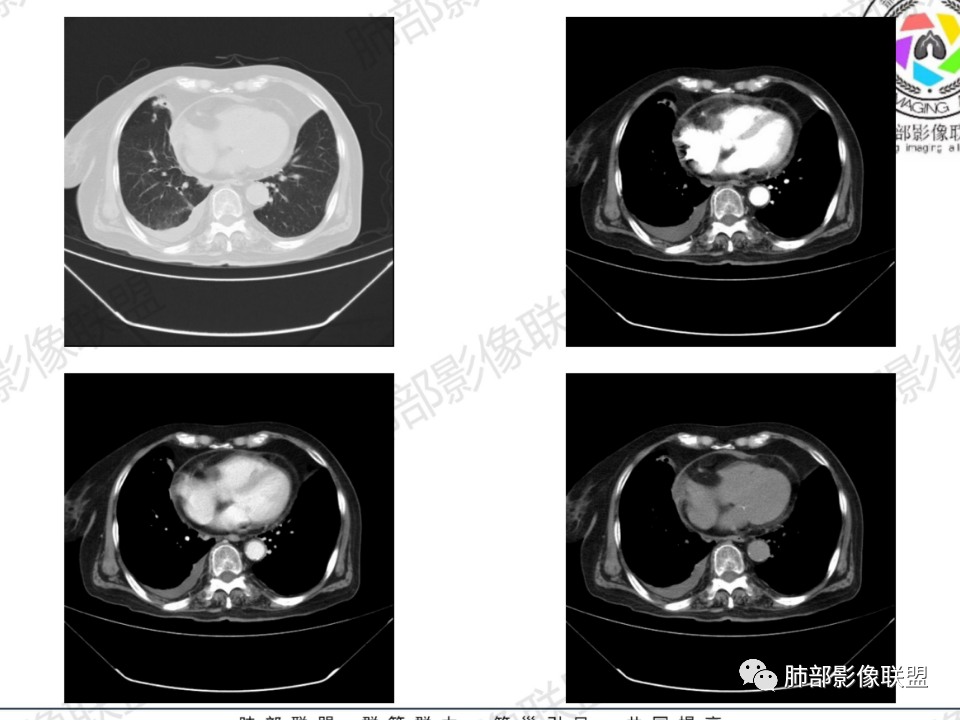

老年患者,病程中等,有咳嗽/喘息/低热症状,肿瘤标志物升高,感染标志物不高,右上肺新生物,中央型,边界清楚,有分叶,支气管截断,内有坏死,不均匀强化,考虑肺癌,鳞癌?

那个人:老年女性,亚急性病程,咳嗽发热。有垂体前叶功能减退,目前激素替代治疗,长期激素,量小,不知道累积量,没有目前激素水平指标。既往有淋巴结结核病史。肿瘤标记物Ca125升高。血沉升高,C反应蛋白轻度异常。影像,右肺上叶靠近肺门团块影,右肺门淋巴结钙化肿大,支气管狭窄,局部增厚,团块影外朝内改变,强化明显,血管破坏不明显,有粘液。和纵隔胸膜分界清楚,周围肺组织有斑片渗出影,右侧胸腔积液,考虑炎性?结核?支气管镜检查除外恶性飞鹰行动:老年患者,影像表现 右肺上叶占位性病变,边界清楚,有分叶征,内见细小钙化,右肺上叶支气管截断,增强病灶不均匀强化,病灶内有条状坏死区(扩张的支气管?),纵膈内未见增大淋巴结,考虑炎性病变,结核可能。一切∮随缘:右肺上叶实性肿块形态不规则,呈三角形,边缘分叶,边界伴有磨玻璃影,近段支气管未见明显显示,可能堵塞,病变平扫密度均匀,增强后可见低密度坏死无强化,周围略强化,右肺下叶散在结节。心包积液,及右侧胸腔积液,临床:有低热,低蛋白血症,肿瘤标记物高,考虑恶性:腺癌,神经内分泌癌(强化偏弱了),淋巴瘤,鉴别:结核红星:老年女性患者右肺上叶,肺门上区 分叶状肿块 ,右肺上叶支气管显示不清,增强扫描肿块,中等程度强化可见小斑片状坏死区,病灶内部可见斑点状钙化灶,病灶周围可见斑片状及小斑点状影,纵膈淋巴结增大,其他区域,胸膜下可见斑点状钙化。考虑肉芽肿性病变,结核的可能性大。老年患者最排除肿瘤性病变腺癌。土娃:右上肺不规则肿块影,边缘分叶,边界磨玻璃影欠清,病灶分叉状,内见点状钙化影及坏死灶,支气管堵塞,病灶增强强化不明显。考虑瘤样结核,鉴别淋巴瘤。张小兵:老年女性,亚急性病程,右肺上叶见不规则肿块,边缘平直凹陷为主,周围GGO边界不清,内见点状钙化及坏死灶,增强持续性渐进强化,右侧少量胸腔积液,双肺门及纵隔肿大淋巴结伴钙化,综合考虑慢性炎症。saf:老年患者,影像表现 右肺上叶占位性病变,边界清楚,有分叶征,增强病灶明显不均匀强化,纵膈内未见增大淋巴结,考虑炎性病变,结核可能。小兜:老年女性,咳嗽喘息一月,发热三天,肿瘤标志物升高,长期激素替代治疗。CT示右肺上叶近肺门不规则实变影,周围伴磨玻璃影,增强持续性渐进强化,内部血管破坏不厉害,内部可见多发条形低密度灶,右侧胸腔可见少量积液,双肺门及纵隔可见钙化淋巴结,考虑为炎性病变,结核可能玫:女,79咳嗽,喘息一月,发热三天入院,右肺上叶不规则形软组织密度肿块影,边界清晰,边缘见分叶及细短毛刺,病灶内见点状钙化影及稍低密度区,病灶边缘呈磨玻璃样改变,增强扫描,病灶呈不均匀性强化,考虑炎性病变,鉴别鳞癌。大雄:老年女性,既往诊断淋巴结结核,提示已治愈,近2年服用激素,诱导结核复燃→发热;纵隔肺门淋巴结肿大钙化,压迫支气管,右肺上中下叶支气管均狭窄→喘息咳嗽;尖段支气管受累闭塞→肺不张、支气管粘液栓;累及胸膜,结核性胸膜炎并胸水→右侧胸痛;实验室,血沉快,CA125高,低蛋白,符合;下一步,支气管镜尖段支气管刷检抗酸染色周太狼:老年女性,亚急性病程,肿瘤标志物升高。CT示右肺上叶尖段不规则肿块影,有分叶、收缩,周围伴磨玻璃影,增强渐进强化,内部可见多发条形低密度灶,右侧胸腔及心包少量积液,纵隔内淋巴结稍增大。倾向于恶性病变,肺癌伴阻塞性炎变可能。丽:老年女性,右肺上叶不规则软组织肿块,边缘清晰,内密度不均,可见点状钙化及粘液栓,周围可见片状高密度影,增强后均匀强化,内多发低密度,纵膈多发钙化淋巴结,考虑结核可能大,建议结合支气管镜检查除外肿瘤宇宙:右胸廓缩小,右肺上叶团块影及不张,平直边,周围磨玻璃影,纤细胸膜牵拉,上叶尖段支气管堵塞,明显延迟强化,可见支气管粘液栓,两肺门钙化淋巴结,右侧胸水,考性炎性肉芽肿,鉴别腺癌王秀仙:右肺上叶肺门区肿块,上叶支气管开口阻塞,形态不规则,密度不均,内可见支气管粘液栓及多发小灶性坏死,周围磨玻璃影边缘模糊,渐进强化,右侧胸腔积液、胸膜钙化,考虑炎性肉芽肿性病变,慢性炎症。鉴别鳞癌,结核。刘丹:老年女性,右肺上叶肿块伴钙化,右肺上叶支气管截断,增强后均匀强化,周边可见点片状模糊影,右侧胸腔积液,右肺门淋巴结增大,考虑占位并阻塞性炎症,肿瘤?结核?建议纤支镜检查。小飞:右肺上叶纵隔旁软组织肿块,边缘深分叶、长毛刺及毛刷样短毛刺,边缘磨玻璃影,磨玻璃边界模糊,支气管截断,平扫密度不均,可见点状钙化,增强不均匀明显强化,心影增大,心包积液,右侧胸腔积液,考虑恶性肿瘤,腺癌?秦化君:右肺上叶不规则分叶软组织密度肿块,边缘清晰,胸膜牵拉,周围花花草草,上叶尖段支气管阻塞,内可见点状钙化,增强后密度不均可见支气管粘液栓及坏死区,内见血管分枝。中间段及中叶,下叶支气管狭窄,壁见钙化。右肺门淋巴结肿大,右侧胸腔积液,心包粘连肥厚。考虑1右上肺恶性病变,鳞癌?2右肺多叶段支气管狭窄,考虑支气管内膜结核?3胸腔积液及肺门淋巴结肿大,转移?风儿:老年女性,右肺上叶肿块,形态不规则,外围大内带小,边缘分叶膨隆平直及毛糙,密度不均,内见支气管粘液栓及多发小灶性坏死,坏死边缘清晰 ,渐进强化,上叶尖段支气管阻塞,叶支气管壁有局限性增厚,邻近胸膜腔微积液;纵隔及双肺门淋巴结肿大,部分钙化,右侧胸腔积液、心包积液、胸膜钙化,考虑炎性,肉芽肿性结核可能性大。鉴别鳞癌,女性及血供均不支持;腺癌,坏死边界太清晰。流心明智:老年女性,79岁,咳嗽、气短1月,发热3天。胸CT:右肺上叶见不规则肿块,边缘有膨隆、有平直凹陷,周围GGO边界不清,病灶内见点状钙化、粘液栓,尖段支气管未见,增强持续性渐进强化,右侧少量胸腔积液,双肺门及纵隔肿大淋巴结伴钙化,肺动脉增粗。考虑:右上叶尖段堵塞并慢性炎症,支气管TB并结石?鉴别Ca

右肺体积小,提示既往结核

支气管影

前,后段都在,没有堵塞

支气管壁增厚,周围磨玻璃边界不清,提示炎症。胸膜下钙化符合结核

近期发热符合感染

这个层面往上应该是尖段,显示不清

背段支气管周围增厚伴钙化,符合结核改变

胸腔积液并胸膜钙化,符合结核;

结核是肯定有。现在最大问题是尖段

近端显示不清,但是远端是粘液栓,可以认为是还行的

如果是近端鳞癌,远端应该会堵塞,不会整个肿块里面还有较为通畅的支气管

这个区域我们看到密度与周围一致,并不是肺癌伴周围不张的感觉,所以鳞癌暂时是不支持的